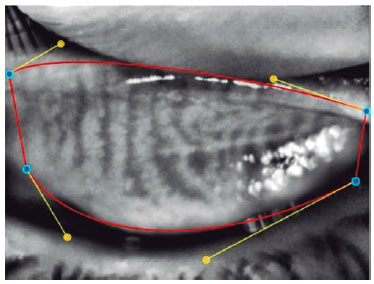

Finally, non-contact meibography was applied to participants’ left eye. This procedure was performed using infrared light with Phoenix meibography imaging software module installed on Sirius (CSO, Florence, Italy) corneal topography device. The participant’s head was placed on the device, and they were asked to look straight ahead. First, the lower eyelid was inverted by pressing on its outer part, and meibomian glands measurements were taken from the tarsal conjunctival surface of the lower eyelid. The same procedure was repeated for the upper eyelid. At least three measurements were made, and the best image obtained was evaluated. During the image analysis, the borders of the eyelids and then those of the meibomian glands were marked using the Phoenix software module (Figure 1 and Figure 2). The meibomian glands loss was automatically calculated using the same software. The result was obtained as percentage loss (Figure 3).

In addition to these findings, in Sirius meibography, the meibomian glands were unevenly distributed, thinner, and less hyperreflective, the gland folds and the distance between the glands increased, and the glands did not extend to the orifices among the participants that smoked e-cigarettes (Figure 4). In contrast, in control group, the meibomian glands were regular and thick, had high hyperreflectivity, and extended to the orifices.